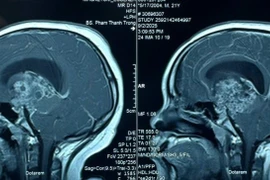

Phẫu thuật khẩn cấp cứu chàng trai 21 tuổi hôn mê sâu do u sọ hầu tái phát

U sọ hầu là loại u não hiếm gặp tuy lành tính nhưng đặc biệt nguy hiểm vì gần vị trí vùng tuyến yên và vùng trên yên.